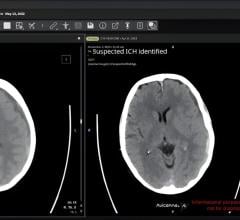

Sept. 3, 2025 — According to ARRS’ American Journal of Roentgenology (AJR), a commercial artificial intelligence (AI) ...